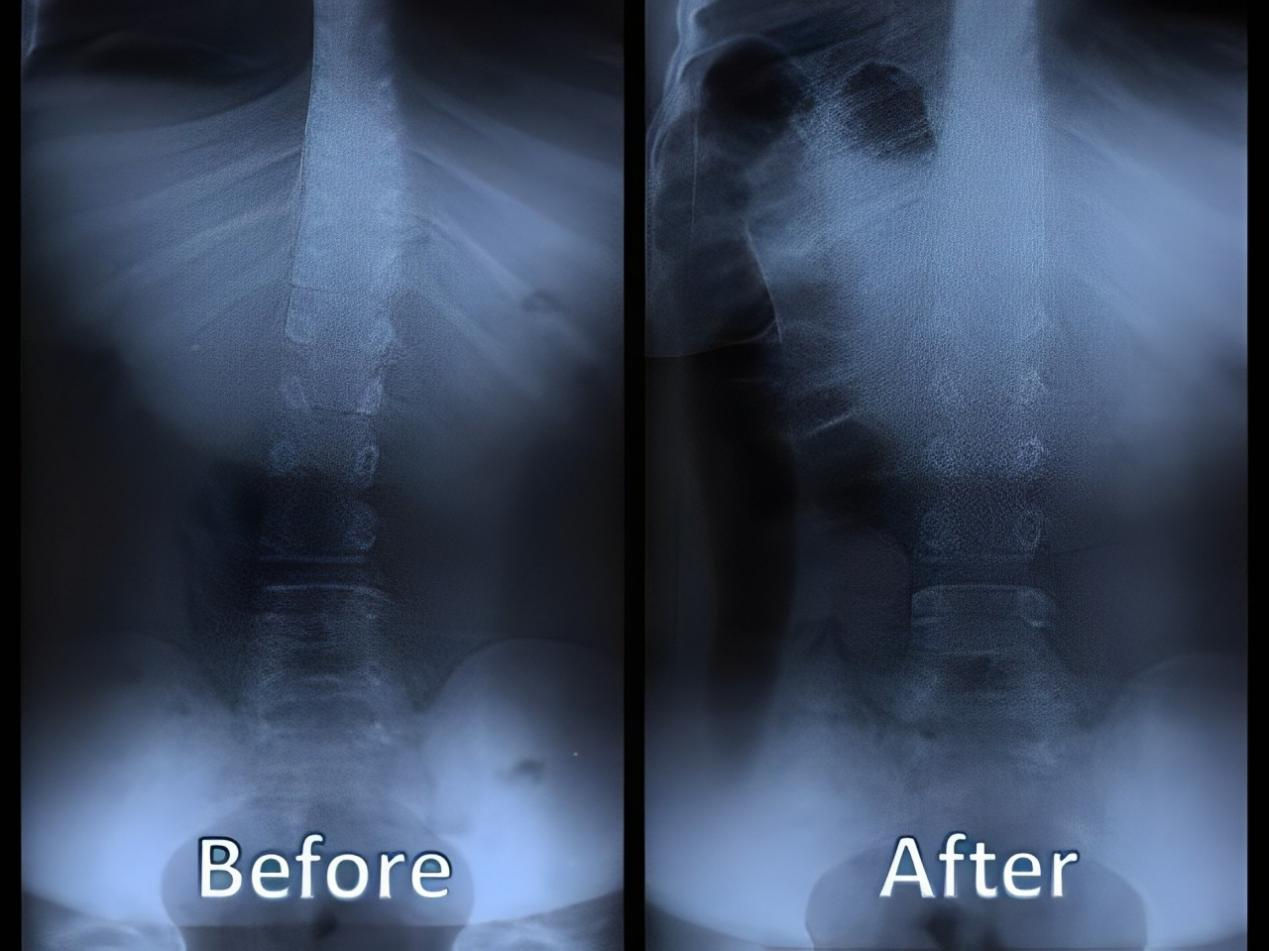

四、 恢復脊椎自然曲度

脊椎整復床的獨特設計能夠幫助恢復脊椎的自然曲度,改善脊椎側彎和不良姿勢,讓您重獲健康體態。

五、矯正完和矯正后的對比案例: